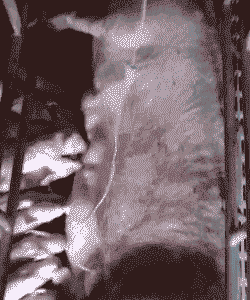

耳静脉输液消炎

第一瓶:0.9%氯化钠生理盐水500ml + 鱼腥草20ml + 林可霉素20-30ml + 地塞米松10mg。

第二瓶:5%葡萄糖500ml + 葡萄糖酸钙2支 + 复合VB。

第三瓶:甲硝唑100-150ml。

控制输液速度:输液速度不宜过快,以免母猪出现呕吐等不良反应。

观察反应:在输液过程中,应密切观察母猪的反应,确保药物使用安全有效。